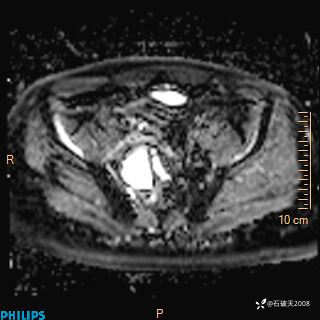

2023年3月份MRI影像

增强轴位